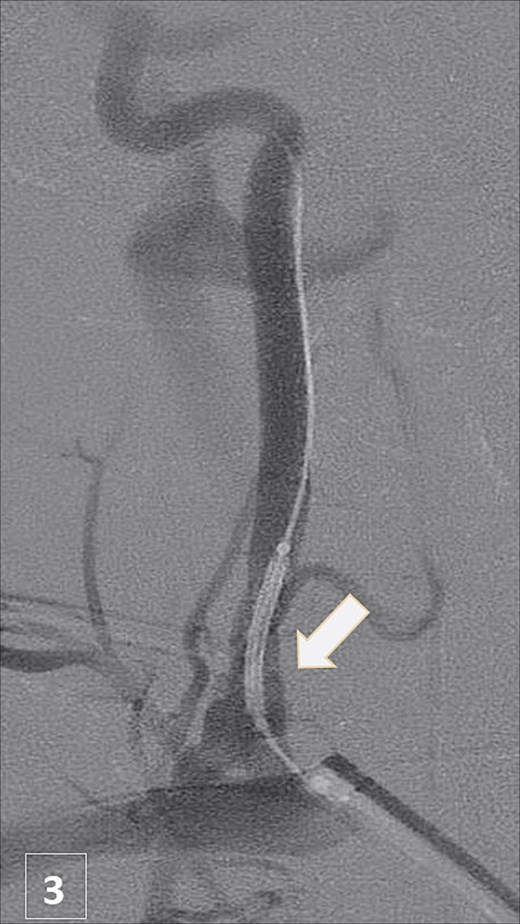

An urgent CTA revealed contrast extravasation from the proximal left vertebral artery, ~1 cm from its origin at the subclavian artery (Fig. 1). He was immediately taken to the angiography suite. Via left brachial access, a balloon-expandable covered stent (4 × 29 mm) was deployed, completely sealing the injury and restoring flow (Fig. 2). Post-procedure imaging confirmed no further extravasation (Fig. 3). The patient stabilized, vasopressors were weaned, and he was discharged without neurologic deficits. The patient’s clinical course and management are summarized in a timeline (Fig. 4).

Post-stent angiogram showing complete sealing of injury with preserved flow.